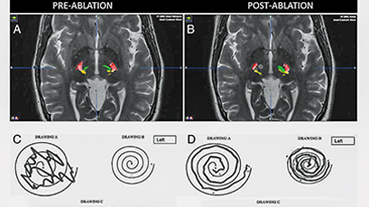

Innovative technologies and alternatives to traditional treatments are transforming the diagnosis and management of neurological conditions. In 2025, NewYork-Presbyterian physicians and surgeons from Columbia and Weill Cornell Medicine used sonication and convection-enhanced delivery to penetrate the blood-brain barrier, validated an adjunctive treatment for subdural hematoma, broadened access to spine surgery, advanced experimental therapies for neurodegenerative diseases, and more. Our specialists have been steadfast in reshaping the fields of neurology and neurosurgery in the pursuit of better patient outcomes and enhanced quality of care.

From cutting-edge research to compassionate patient practice, neurologists and neurosurgeons from Columbia and Weill Cornell Medicine are at the forefront of developing and applying the most advanced approaches to treat debilitating conditions affecting the brain and spine. With a broad range of focus on neurodegenerative and neurovascular disorders to malignant tumors, our innovative and advanced care is leading to new treatment options and enabling patients to achieve the best possible outcomes.